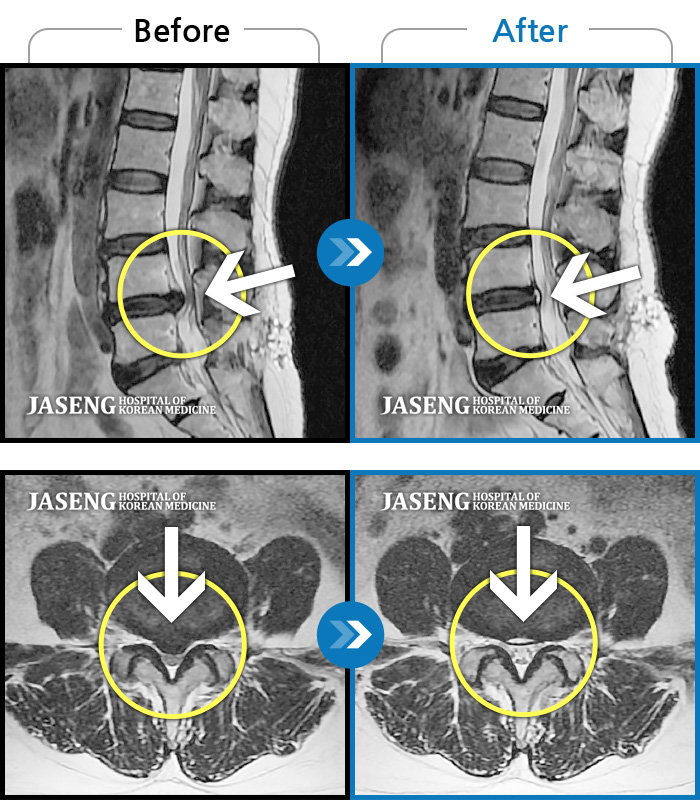

MRI사진에서 좋아지고 있다는 말씀에 넘 기뻤습니다^_^